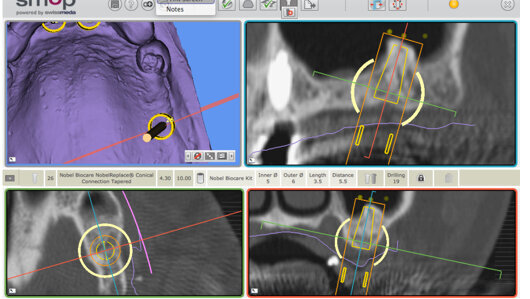

Le développement de la radiologie dentaire a vu l’introduction de la Tomographie Volumique à Faisceau Conique (TVFC ou Cone Beam Computerized Tomography, CBCT) dans le début des années 1990. Un implant virtuel pouvait être déplacé le long de la crête osseuse afin de déterminer si le volume osseux était suffisant pour placer un implant, ou si une greffe osseuse était nécessaire. D’autres avancées ont permis d’ajouter l’anatomie dentaire et les tissus mous, ainsi que le wax-up de la future restauration, dans la même plateforme numérique. Au début des années 2000, quelques systèmes étaient disponibles. Aujourd’hui, la plupart des principaux systèmes implantaires offrent la possibilité d’élaborer le plan chirurgical et de produire le guide.7

Après l’intégration des trois composantes de la phase diagnostique dans le logiciel (anatomie de surface, wax-up et examen radiologique), le logiciel de planification permet le positionnement virtuel des implants selon l’objectif prothétique final et l’anatomie osseuse existante. Il permet souvent de détecter un volume osseux insuffisant ce qui peut aider le clinicien dans sa décision d’utiliser un implant spécifique avant la chirurgie. Des paramètres tels que l’angulation de l’implant, la position, l’espace prothétique et la distance entre les implants, peuvent faciliter la pose adéquate de l’implant. L’identification des structures anatomiques importantes permet en outre d’éviter ces obstacles au cours de la chirurgie.10–13